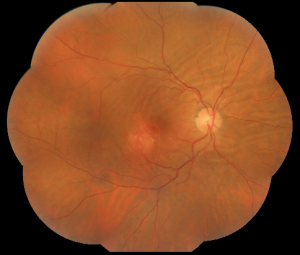

Choroidal folds are lines, grooves or striae predominantly involving the posterior pole of the eye which appear as alternating light and dark lines on fluorescein angiography. They are often arranged in a parallel and horizontal fashion but may be vertical, oblique, or irregular. These folds reflect the undulations of the choroid, retinal pigment epithelium (RPE) and the overlying neurosensory retina and tend to vary in length and width, rarely extending beyond the equator.[1] [2] [3] [4]

The diagnosis is made mainly by fluorescein angiography, wherein the folds appear as a series of alternating hyperfluorescent and hypofluorescent streaks starting early in the arteriovenous phase, persisting through the late venous phase, and not leaking in the late films. The hyperfluorescent areas correspond to the peaks of the choroidal folds, and the hypofluorescent areas to the valleys.[3]

Fluorescein angiography cannot differentiate chorioretinal from choroidal folds, but the optical coherence tomography (OCT) patterns of the two are strikingly different although these are not completely singular entities. In cases of chorioretinal folds, OCT shows that the retina, RPE and choroid are all folded in a similar manner and maintain their normal relationships and apparently normal thickness, although a certain flattening of the inner retina can be seen along the crests, whereas choroidal folds correspond to undulations of the hyperreflective line corresponding to the RPE as well as the underlying choroid with a flat or nearly flat retinal surface with a variable retinal thickness variable, increasing in correspondence to the valleys and reducing in the crests. The retina, which has a softer structure, adapts itself to the wrinkling to preserve a flat inner surface.[19] The severity of choroidal folds have been staged on the basis of FA imaging. [28]